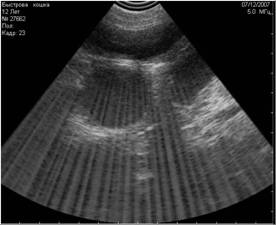

- сетевые - вызванные включёнием одновременно с УЗИ-аппаратом электрических приборов и сотовым телефоном (Рис.1; 2);

Рис1. Помехи, вызванные включённым рядом с аппаратом УЗИ сотовым телефоном. Во избежание этого лучше просить владельца выключать сотовый телефон при проведении ультразвукового исследования. |

Рис2. Помехи, вызванные работающими электроприборами, включёнными в сеть рядом с аппаратом УЗИ. |